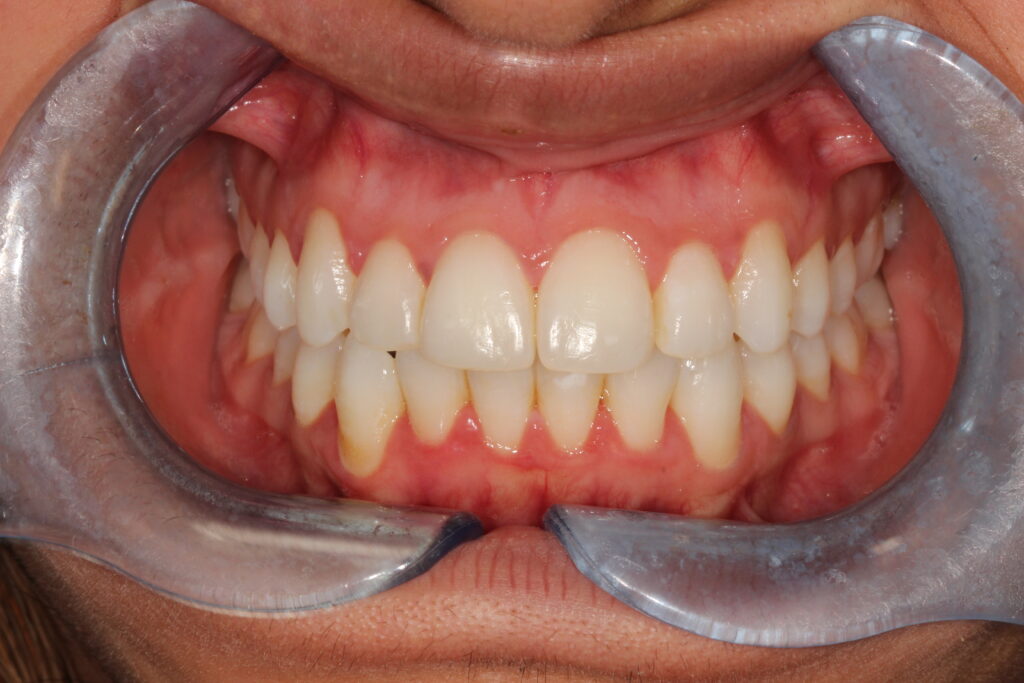

Smile Gallery

Brighten your smile, lift your confidence.

This gallery showcases real results at Goldsworth Road Dental & Implant Centre achieved with Air Polishing designed to look beautifully natural.

after hygiene

Before hygiene

Before

After